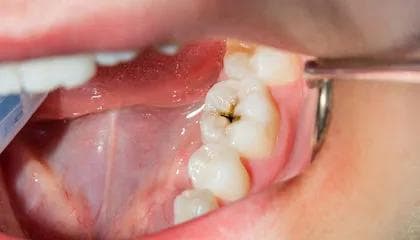

Karies

Karies medfører små hull til å begynne med. Disse er vanligvis ikke smertefulle, men om hullet får utvikle seg og blir dypt, kan du kjenne ising når du drikker eller spiser noe kaldt, eller puster inn kald luft.

Du bør oppsøke tannlege så raskt som mulig for behandling av hullet, men om smertene ikke er for sterke og kan behandles med reseptfrie smertestillende til du får en time, har du ikke behov for akutt tannlege.